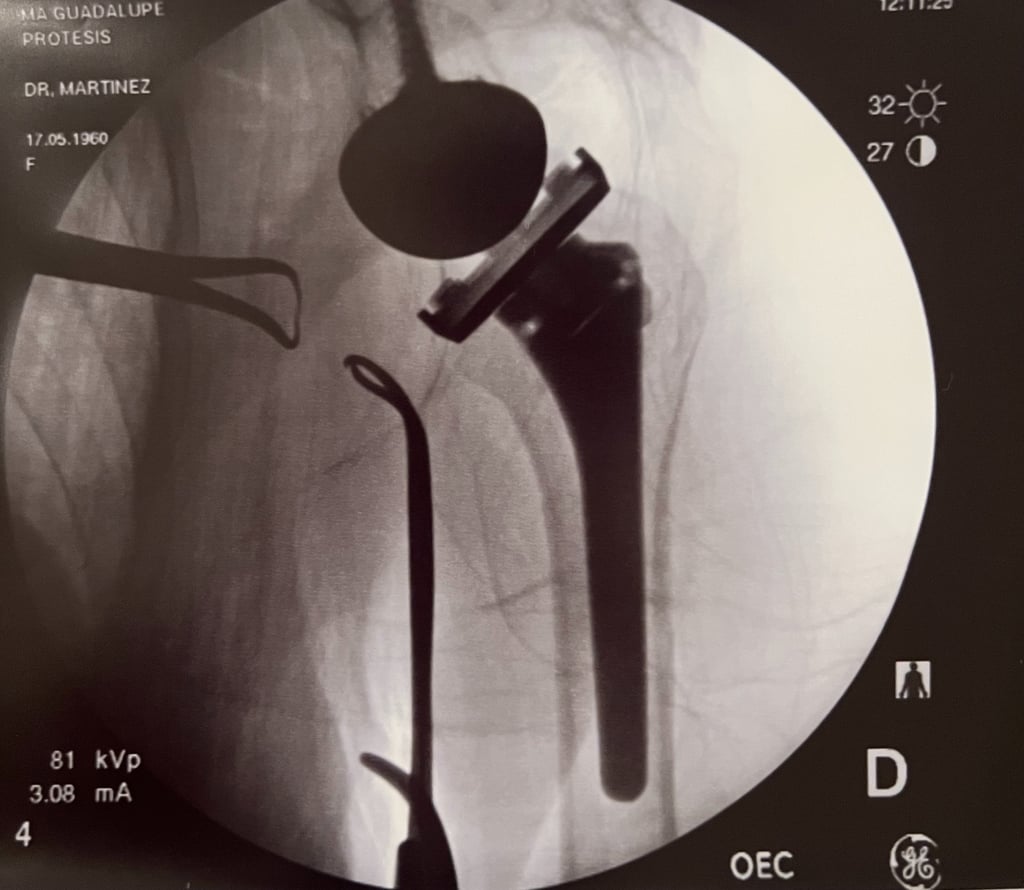

Control de radiografía de prótesis reversa de hombro.